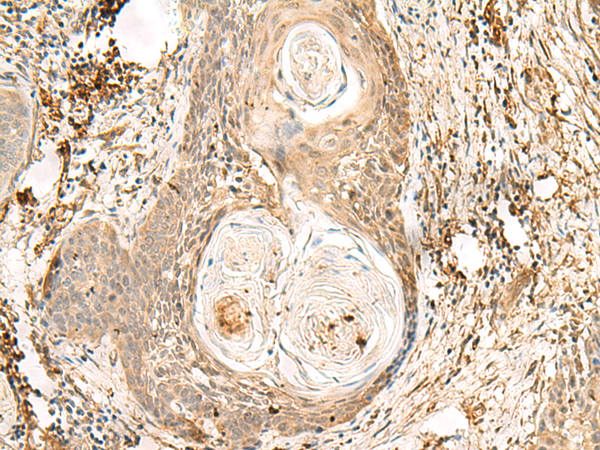

分类: 科研抗体货号: P09887别名: ZNF47; ZSCAN15应用: IHC反应种属: Human